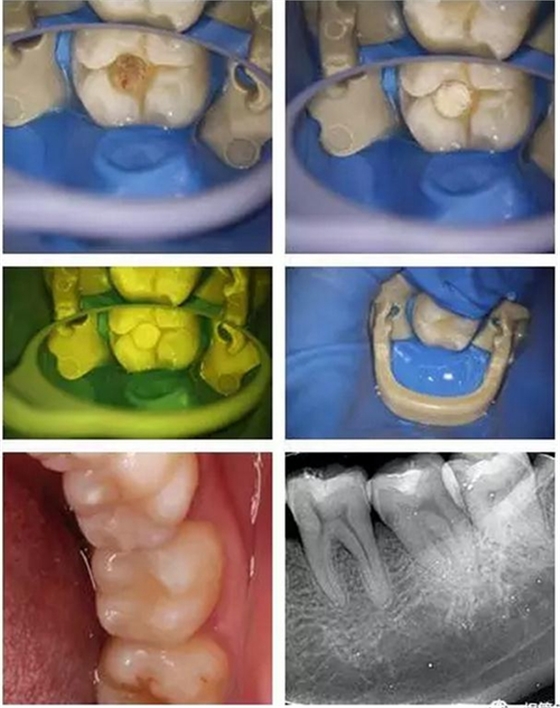

顯微鏡下非常精確與清晰的去凈齲壞組織,精細(xì)的操作盡最大程度保留剩余健康牙本質(zhì),這也需要醫(yī)生精湛的技術(shù)!

所以當(dāng)蛀牙的最前沿非常接近牙髓(比如小于0.5mm時)或者已經(jīng)穿通牙髓時,醫(yī)生在顯微鏡下可見透紅或者出血點時,細(xì)菌就可能已經(jīng)入侵到牙髓組織,這時即便在我們沒有自覺疼痛癥狀時,保髓的難度和風(fēng)險就急劇加大了。這時,醫(yī)生需要結(jié)合患者的臨床癥狀、體征以及術(shù)中所見等來綜合決定患牙牙髓的保存與否以及如何保髓了。

(這就是一個直接穿髓以后,喻剛醫(yī)生根據(jù)情況決定保髓的成功病例,不過這里要非常感謝現(xiàn)在我們擁有的一些新型的生物材料,大大提高了我們保髓治療的成功率!)

美學(xué)樹脂分層堆塑,還原本真!